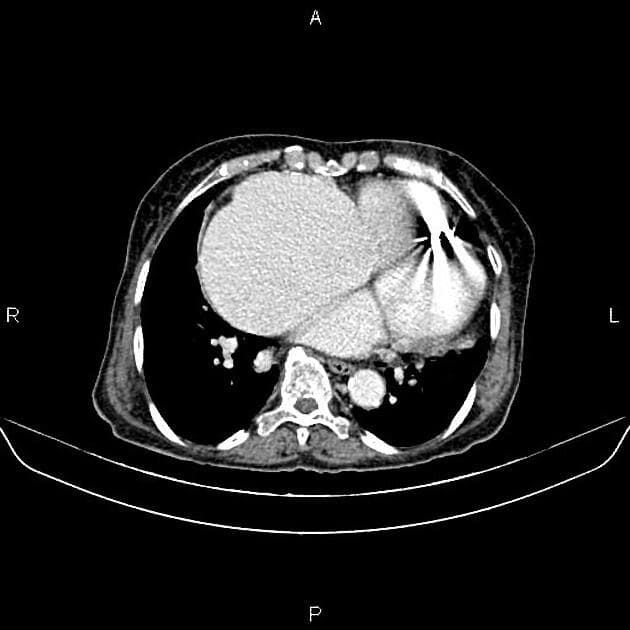

Axial C+ portal venous phase

- Tổn thương dạng nang ở tiểu não với thành nang không ngấm thuốc và nốt thành nang tăng sinh mạch rõ rệt bắt thuốc mạnh: u mạch bào (hemangioblastoma)

- "Chẩn đoán hình ảnh thường cho thấy tổn thương nang ở tiểu não với nốt thành nang tăng đậm rõ rệt, dấu hiệu điển hình của u mạch bào."

U mạch bào là một khối u lành tính, giàu mạch máu ở hệ thần kinh trung ương, thường xuất phát ở tiểu não. Khối u này thường liên quan đến hội chứng von Hippel-Lindau, một bệnh lý di truyền do đột biến gen VHL trên nhiễm sắc thể 3p. Các trường hợp tự phát chiếm khoảng 60–70% tổng số u mạch bào, trong khi 30–40% còn lại xảy ra trong bối cảnh hội chứng VHL, thường biểu hiện với nhiều khối u và khởi phát sớm hơn. Về hình ảnh học, u mạch bào điển hình hiện diện như một tổn thương nang với nốt thành nang tăng đậm rõ rệt, phản ánh tính chất giàu mạch của khối u. Chẩn đoán phân biệt bao gồm di căn (đặc biệt từ ung thư biểu mô tế bào thận), u sao bào dạng nang cuộn và áp xe. Chẩn đoán xác định được thực hiện qua giải phẫu bệnh, cho thấy các tế bào nền có bào tương trong và mạng lưới mao mạch phong phú. Điều trị chủ yếu là phẫu thuật cắt bỏ, thường mang tính chữa khỏi, đặc biệt với các tổn thương đơn độc. Với bệnh nhân VHL, cần theo dõi lâu dài do nguy cơ phát triển thêm các khối u khác.